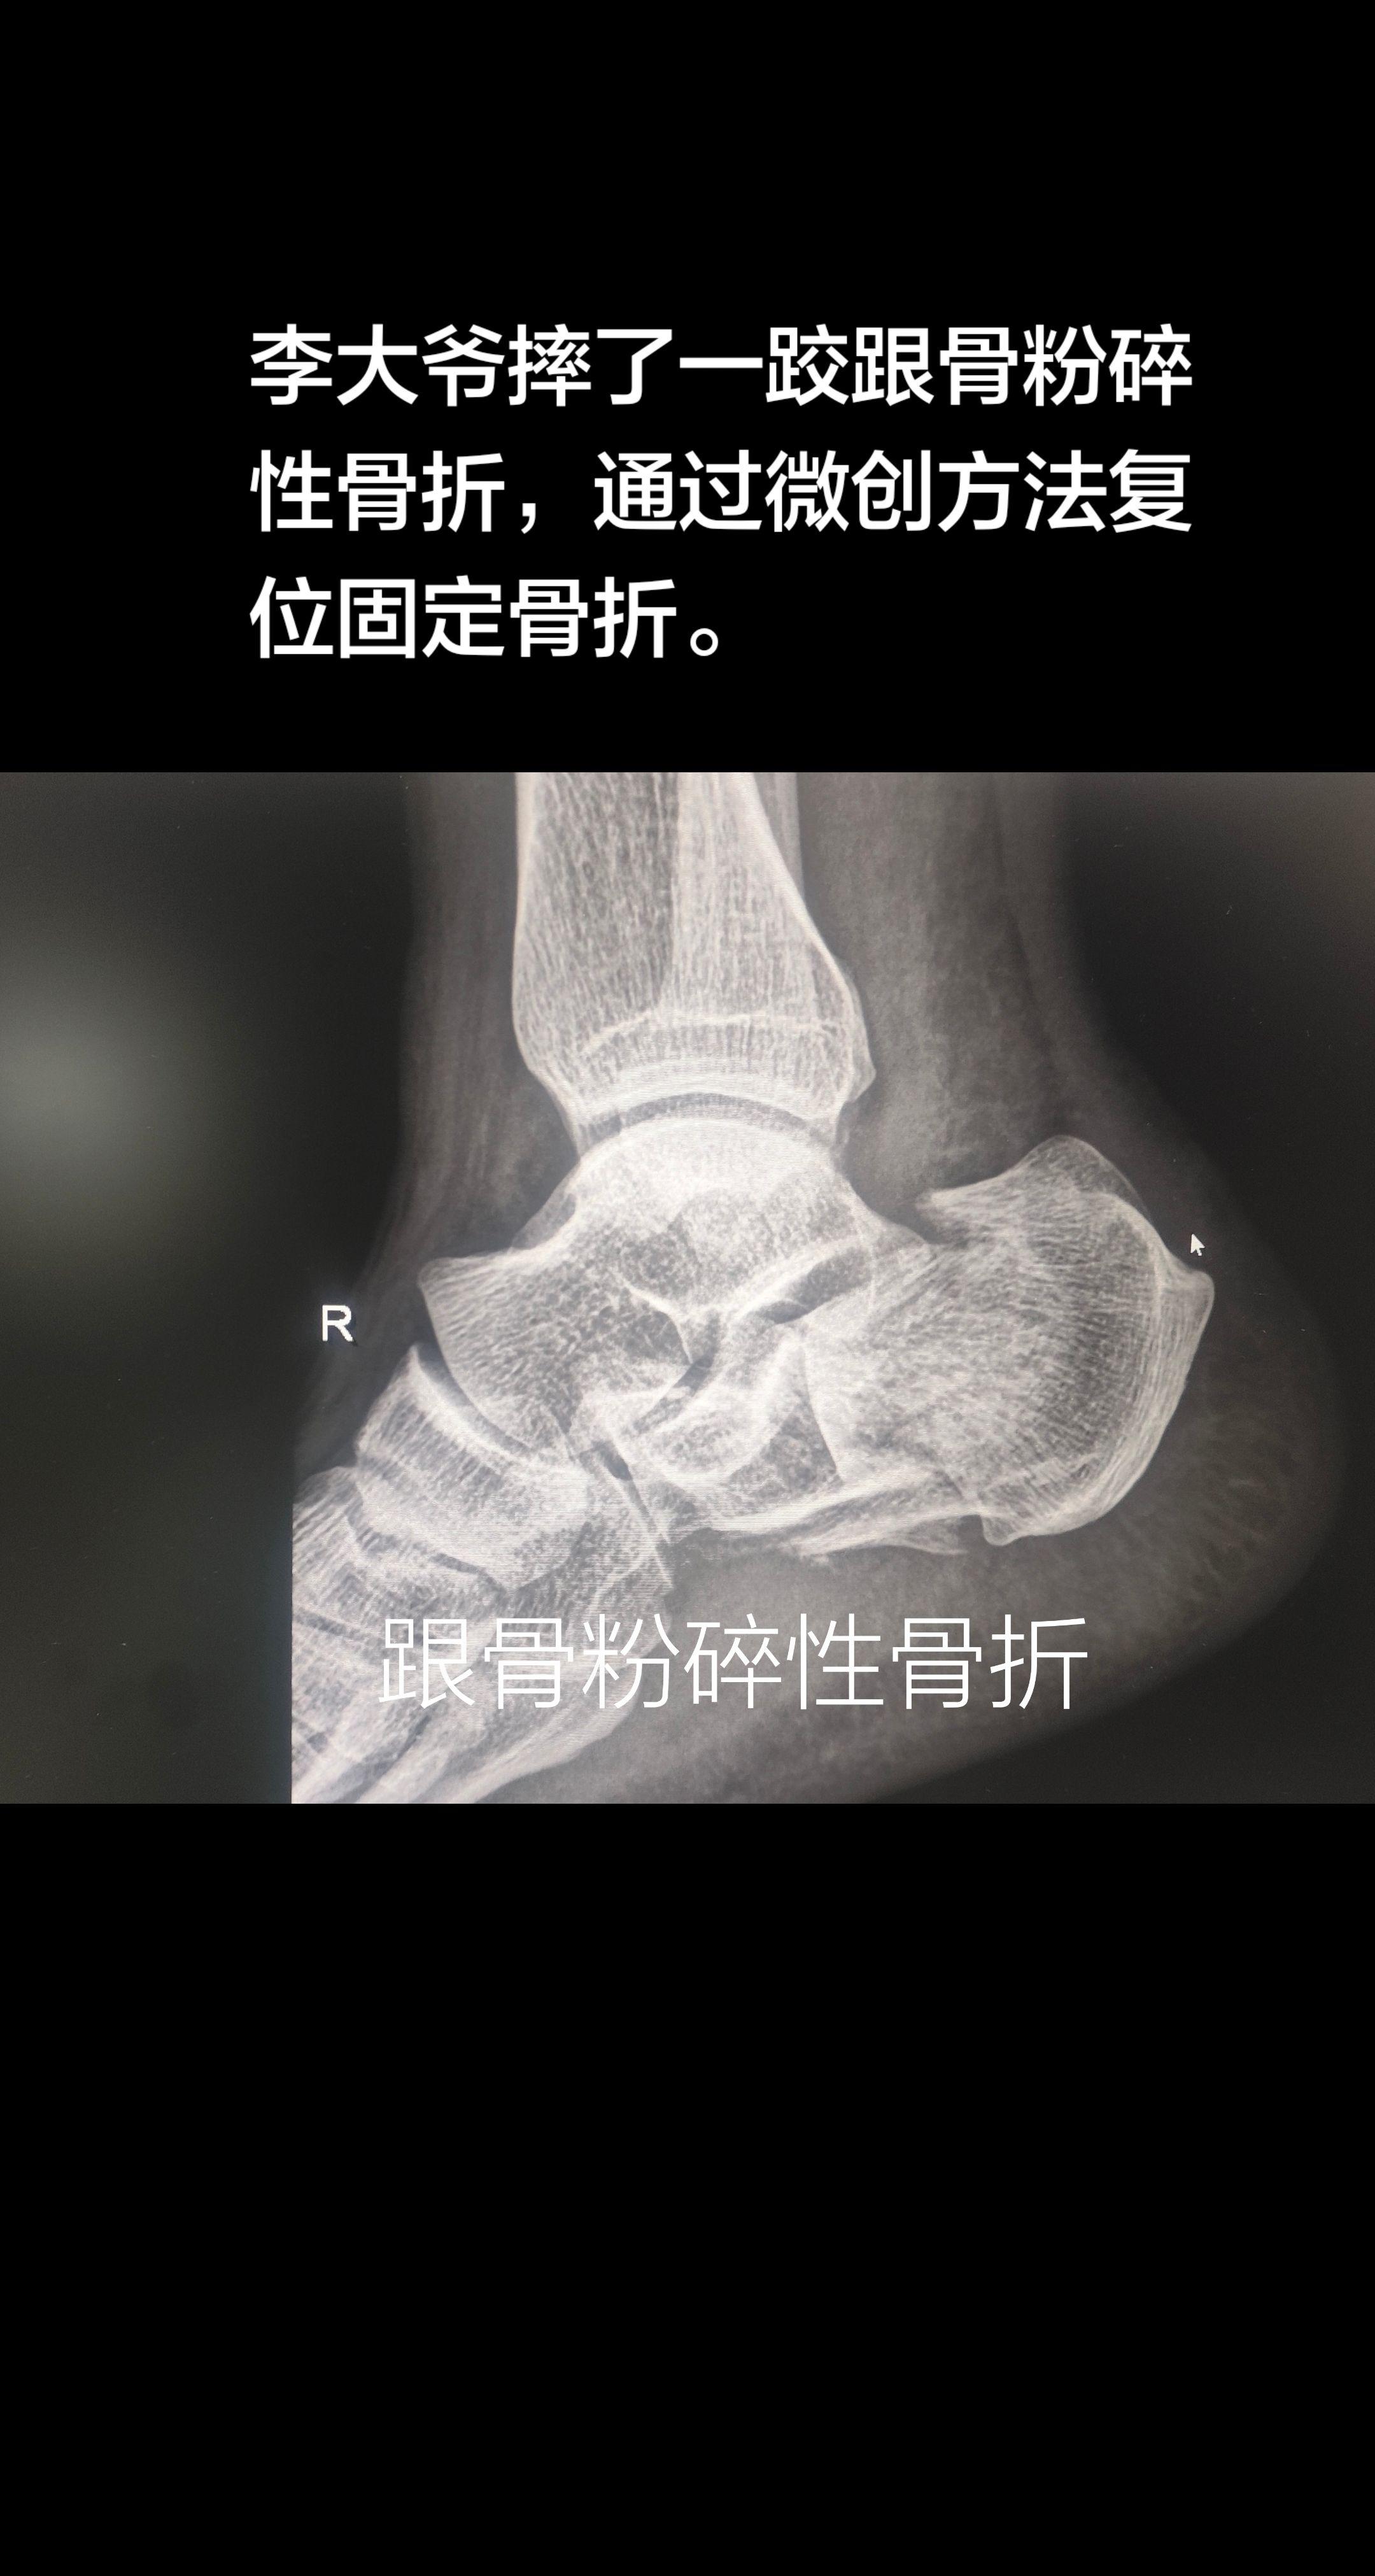

跟骨骨折。